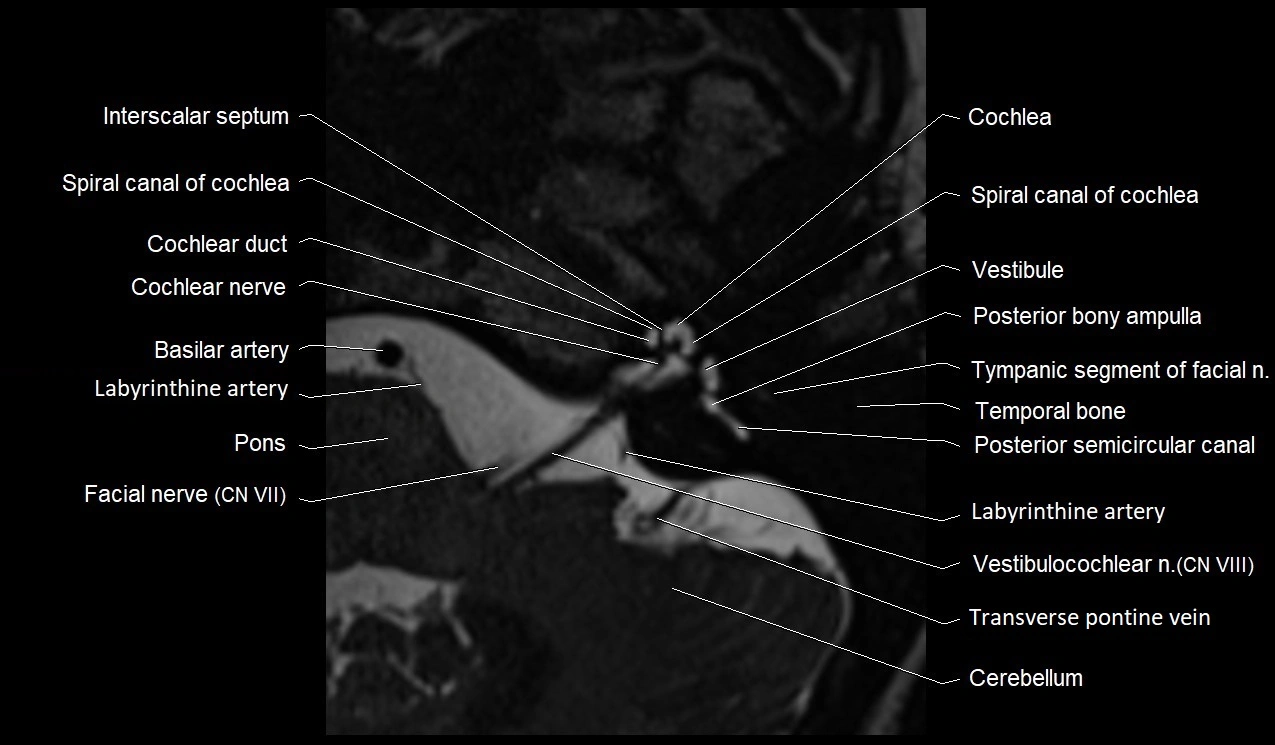

MRI Appearance

• The abducens nerve is a small, thin, linear structure

• Best visualized on high-resolution T2-weighted 3D MRI sequences (e.g., FIESTA or CISS)

• Seen as a hypointense (dark) line running from the brainstem at the pontomedullary junction, traversing the prepontine cistern, and entering Dorello’s canal under the petrosphenoidal ligament, then into the cavernous sinus, and finally the orbit

• May be challenging to visualize in standard MRI due to its small size

• Pathology may be inferred by absence, displacement, or enhancement of the nerve